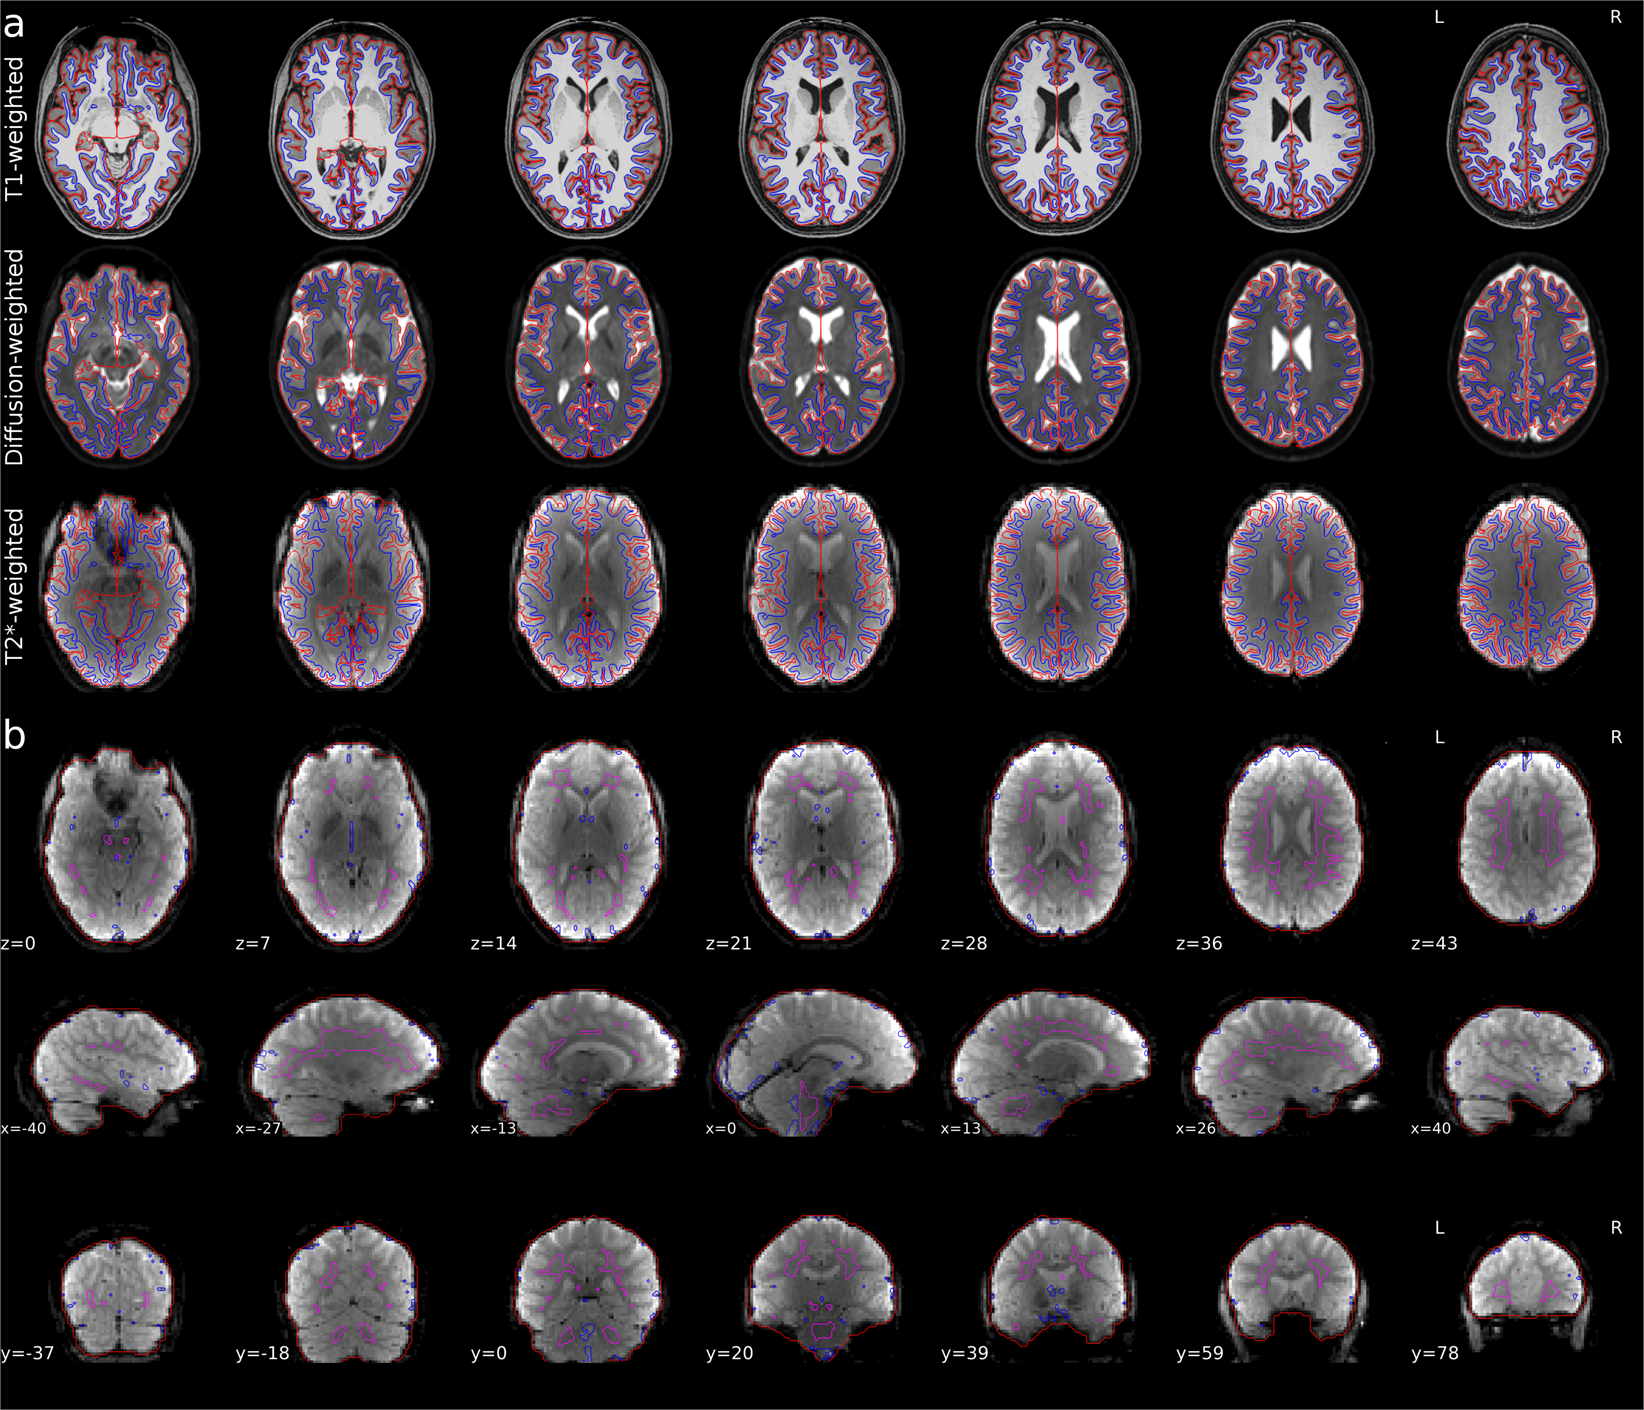

Fig. 2

From: CHIASM, the human brain albinism and achiasma MRI dataset

Qualitative overview of preprocessing for a representative participant (CON1). (a) Axial view of surfaces of white and pial matter (blue and red color, respectively) overlaid on T1w (top row), non-diffusion weighted (b0; middle row) and fMRI (T2*; bottom row) images. (b) Axial (top row), sagittal (middle row) and coronal (bottom row) views of fMRI images. The red contour marks brain mask estimated from BOLD signal, magenta contour marks combined CSD and WM masks, where voxels with partial GM volume were removed, blue contour marks the top 2% most variable voxels within brain mask.